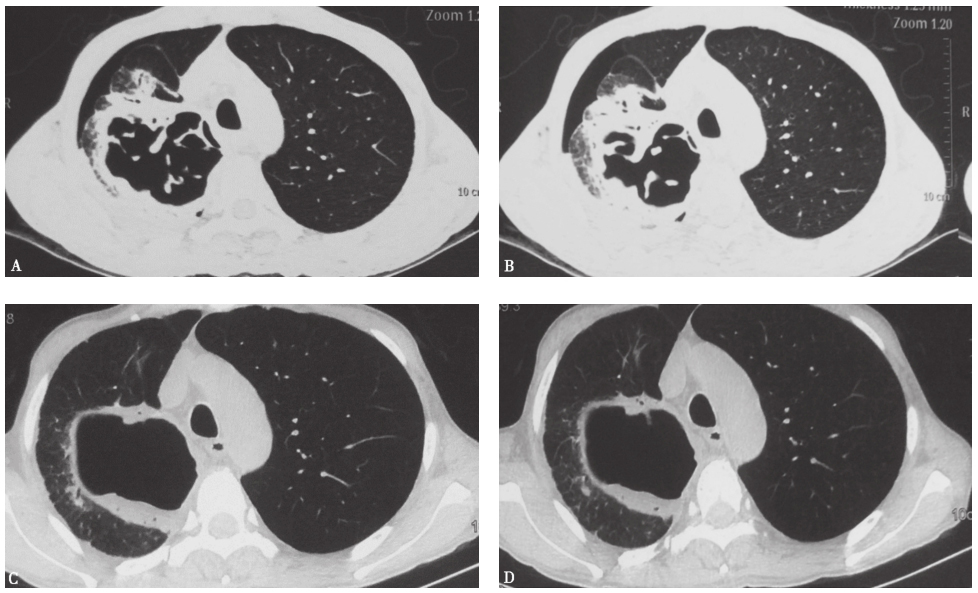

胸部CT:左肺下叶病灶边界较为清楚,表现为实变、空洞,空腔病灶内有液平(图13),其脓液界面呈类蜂窝状气囊影改变。

图13 入院后胸部CT表现(发病后37天)

患者入院后所做系列检查显示:①血沉较入院前明显增快,提示原有病变仍在加重;②自身抗体均阴性,结合临床表现,基本可以排除风湿免疫病;③多次支气管镜检查均见肺内气道通畅,未见任何阻塞征象,故基本可以排除因阻塞性原因导致的阻塞性肺炎,但BALF炎性细胞分类中性粒细胞明显增高仍提示细菌感染的可能;④胸部CT可见病灶转变过程为“渗出实变→囊性病灶融合→坏死液化→脓肿液平形成”;⑤常规病原学检查均阴性。这些结果支持本例患者有感染性疾病的可能。此时,还需要思考以下问题:

解剖左下肺切除病灶发现,结核性肺脓肿腔内气体与大量黏稠脓液和坏死组织在脓液界面之间形成数个张力性小气泡,遂在脓液层面形成类蜂窝样气囊的特殊影像特征。